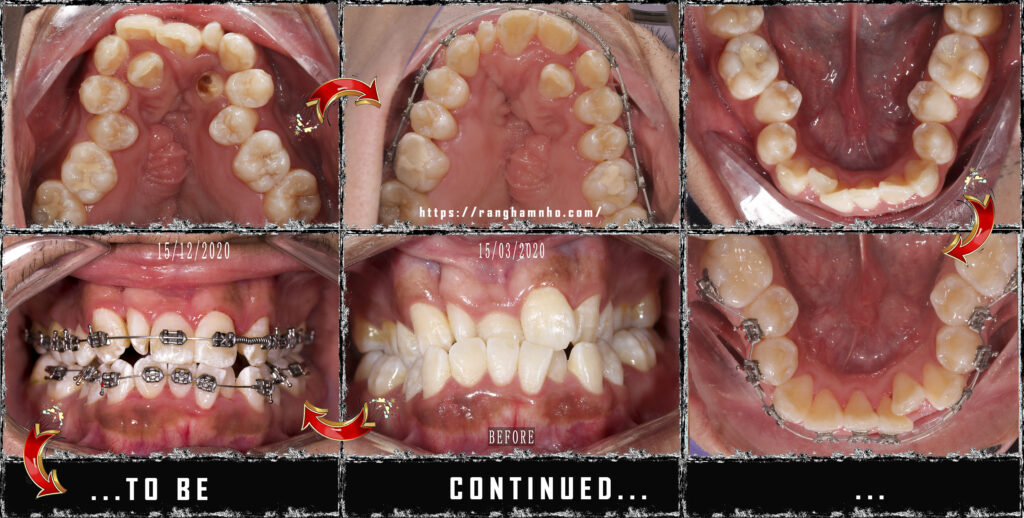

Hẹp hàm là tình trạng kích thước cung hàm tại vị răng 3 và vị trí răng 6 nhỏ dưới chuẩn trung bình so với định mức trung bình theo giới và chủng tộc nhất định. Trên lâm sàng, tình trạng hẹp hàm dễ dàng nhận thấy với việc các răng chen chúc nhiều, kích thước xương hàm trên và xương hàm dưới không tương xứng dẫn đến khớp cắn chéo, khớp cắn kéo.

Khi hàm hẹp, nong bằng dây cung là kĩ thuật đơn giản nhất, phức tạp hơn là các khí cụ ốc nong nhanh, quad helix…..tùy mức độ hẹp hàm và tình trạng lâm sàng, tuổi, giới…. mà có những chỉ định khác nhau.